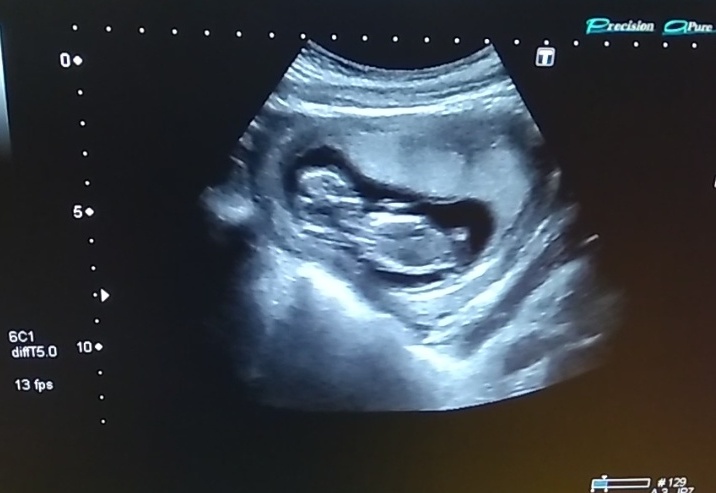

Первый скрининг, УЗИ💕

УЗИ, КТГ, доплерСходили на скрининг, всё хорошо слава богу!))

Твп, носик, ручки, ножки и все органы на месте и в норме 🙏Кровь взяли.

Предположили девочку 👧❣️ Сказали, если ничего не отрастёт ко 2му скринингу, то будет девочка 😂😍

Пдр на 18.03.2021, хотя по М дата красивее 21.03.2021)))